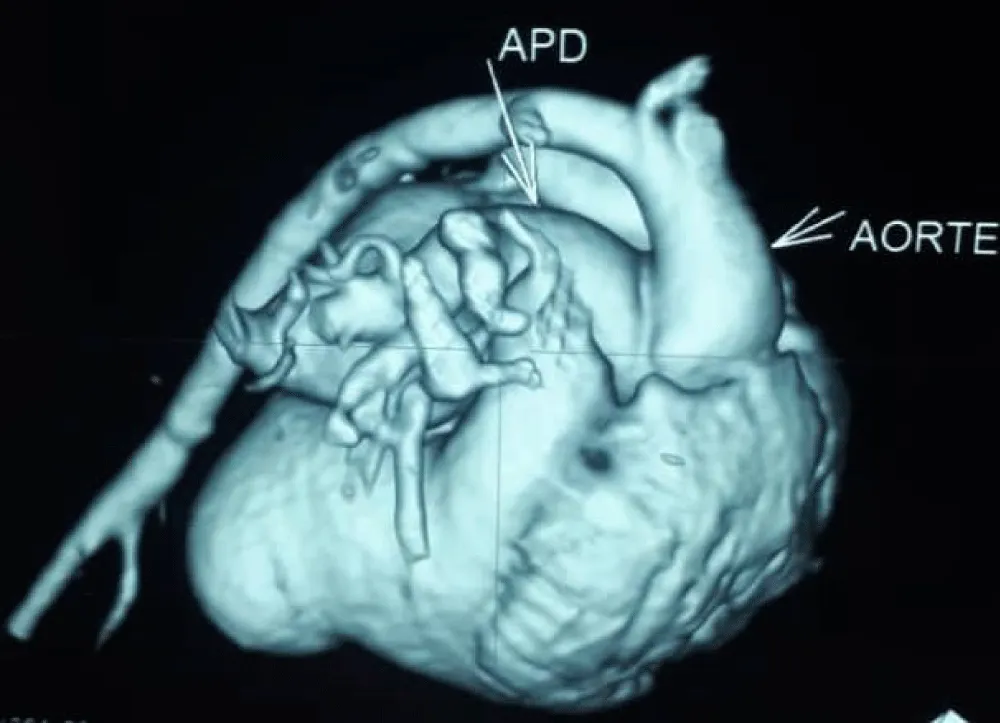

Figure 3: Right pulmonary artery arising from the aorta on cardiac angioscan./p>

The electrocardiogram showed bi-atrial and left ventricular hypertrophy. On frontal telethorax, cardiomegaly with a supra-diaphragmatic peak, a right inferior arch overhang, and peri-hilar vascular overload, predominantly on the right. Cardiac ultrasound revealed a situs solitus heart with levocardia. The aorta normally emerges from the left ventricle, without obstruction. After a few centimeters, it gave way to a right pulmonary artery that filled correctly in systole without obstruction (Figures 1,2). The left pulmonary artery arises directly from the right ventricle. All cardiac cavities are dilated—suprasystemic pulmonary hypertension with ostium secundum-type atrial septal defect with right-to-left shunt. Cardiac angioscan confirmed the diagnosis, showing a 13 mm right pulmonary artery arising from the aorta. The left pulmonary artery arises directly from the right ventricle and measures 9.73 mm, with a functional pulmonary valve (Figures 3,4). Biological tests revealed microcytic hypochromic anemia at 9.3 g/dl. Medical treatment was based on furosemide, captopril, and spironolactone. A surgical cure after catheterization with reimplantation of the right pulmonary artery was indicated. The child died before surgery.